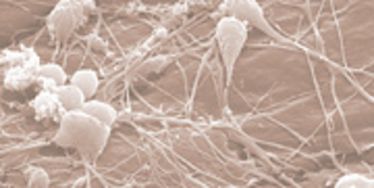

OP-Kurs "Mikrochirurgie der peripheren Nerven und Gefäße"

OP-Kurs "Mikrochirurgie der peripheren Nerven und Gefäße"